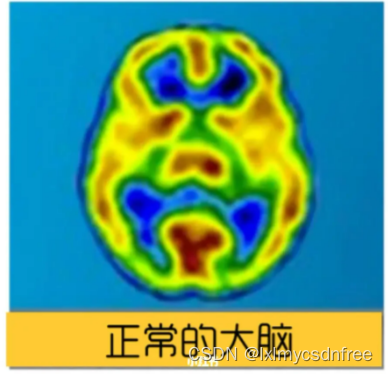

【脑结构的改变、认知变化】在焦虑的大脑中,杏仁核变得很大,回异常活跃;大脑中,除了杏仁核,还有额叶参与了焦虑的处理。杏仁核是情绪大脑的一部分。额叶就是认知大脑。只有当来自情绪大脑的信号压倒认知大脑并进入我们的意识时,我们才会感到焦虑。当杏仁核发出注意危险的警报时,前额叶皮层(PFC)应该像理性的顾问,启动分析处理信息,并帮你做出理性、合乎逻辑的反应。这个过程就像是踩刹车,抑制了被杏仁核夸大的信号。焦虑减弱了大脑部分联结,让理性反应受影响,焦虑会削弱杏仁核和前额叶皮层(PFC)之间的联系,这使杏仁核的刹车受损。焦虑也加强了大脑另一部分联结,使负面记忆留存,长期焦虑的大脑的海马体和杏仁核之间的连接性变得更强。其实当你焦虑时,压力会使大脑中处理长期和情境记忆的海马体收缩。海马体萎缩后,你的大脑保持记忆会有一定困难。然而麻烦的是,当你的海马体与杏仁核的联系比它与前额叶皮层的联系更紧密时,海马体就会保留与焦虑相关的记忆,可能记住的就是那些威胁、失败、危险,而不是存住快乐、成功和安.全的记忆。这会让你更加感到焦虑。